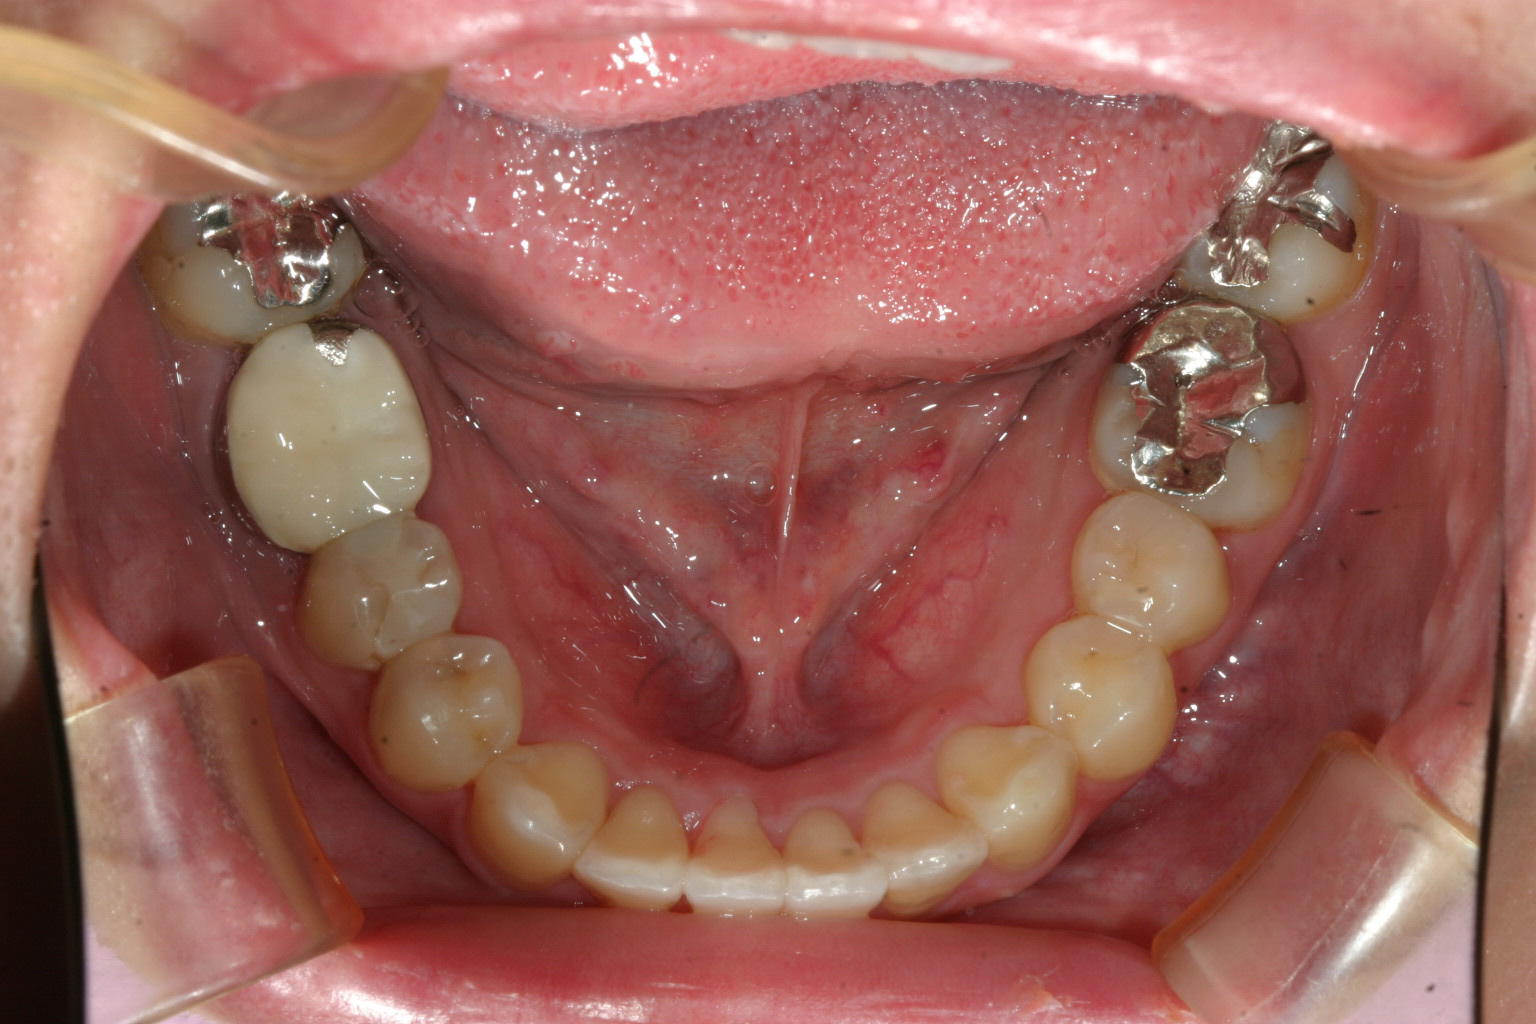

ねじれも改善し綺麗になりました。

こちらのガタガタも綺麗に改善んしてます。

前歯の出加減も最高です。

こちらの症例は前歯のねじれと叢生の改善です。

患者様が一生懸命時間をかけてご自分の歯に向き合って頂いた結果が十分に並びの改善に反映されています。

凄く短期間で綺麗に改善されたケースです。